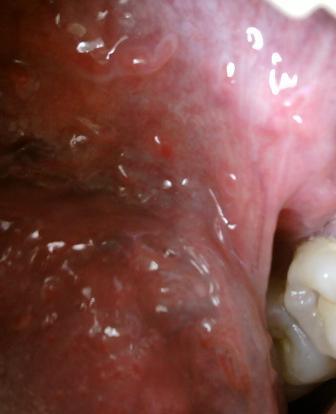

石家庄九州皮肤病医院 > 尖锐湿疣 > > > 肛门尖锐湿疣治疗方法有哪些提到尖锐湿疣相信现在大家已经不再陌生了,他就是现在比较常发的性病之一,并且在性病中的发病率也是你比较高的,在这里专家温馨提示:对于疾病的诊治,应该引起重视,切记不可以耽误诊治。

肛门尖锐湿疣治疗方法有哪些对于尖锐湿疣疾病的治疗应该注意两点;第一点就是去除湿疣体,第二点就是消灭病毒,双管齐下,才能达到比较理想的饿治疗效果,希望大家应该了解。尖锐湿疣具有一定的潜伏期,不易被发觉,尖锐湿疣患者要早发现、早治疗。尖锐湿疣患者在治疗期间,避免再次发生性行为,如果长时间得不到及时有效的治疗,疾病就会逐渐加重,进而会错失治疗的最佳时期。

肛门尖锐湿疣治疗方法有哪些尖锐湿疣的危害是比较大的,如果久治不愈,就会诱发肛门癌变。以上就是石家庄九洲皮肤病医院专家的观点,希望可以帮助到您,如有任何不理解的情随时拨打石家庄性病医院九洲康复热线:66560637这里有专家24小时为您答疑解惑。在这里预祝广大患者朋友们可以早日康复,远离病痛的折磨。